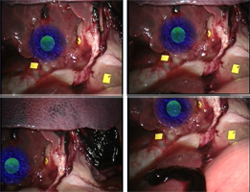

Dynamic View Expansion for Minimally Invasive Surgery using Simultaneous Localization And Mapping

Navigation during Minimally Invasive Surgery (MIS) has recognized difficulties due to limited field-of-view, off-axis visualization and loss of direct 3D vision. This can cause ...